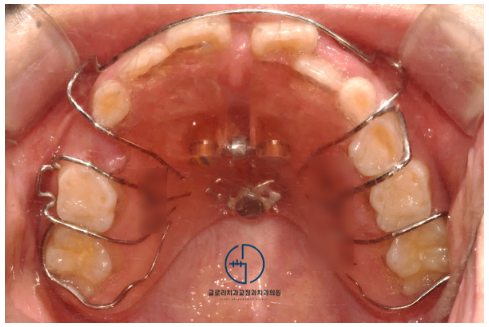

앞서 계획했던 대로

장치를 제작하여 전치 공간을 확보하기로 했습니다.

아래쪽에는 장치를 부착하지 않고

위쪽에만 이동을 돕기로 계획을 세웠죠.

수개월의 시간이 흐르고

과연 어떤 모습으로 바뀌었을지!

삐뚤빼뚤한 치아가 가지런히 배열되었으며

교합 간섭 또한 개선되어 방해를 받지 않고 있었습니다.

전체적으로 문제가 있었던 좌측을 보면

반대교합이 개선된 것을 확인할 수 있었는데요.

이와 더불어, 중심선도 알맞게 잘 맞고 있었습니다.